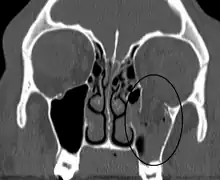

An orbital blowout fracture of the floor of the left orbit.

Thin cut (2-3mm) CT scan with axial and coronal view is the optimal study of choice for orbital fractures.[16][17]